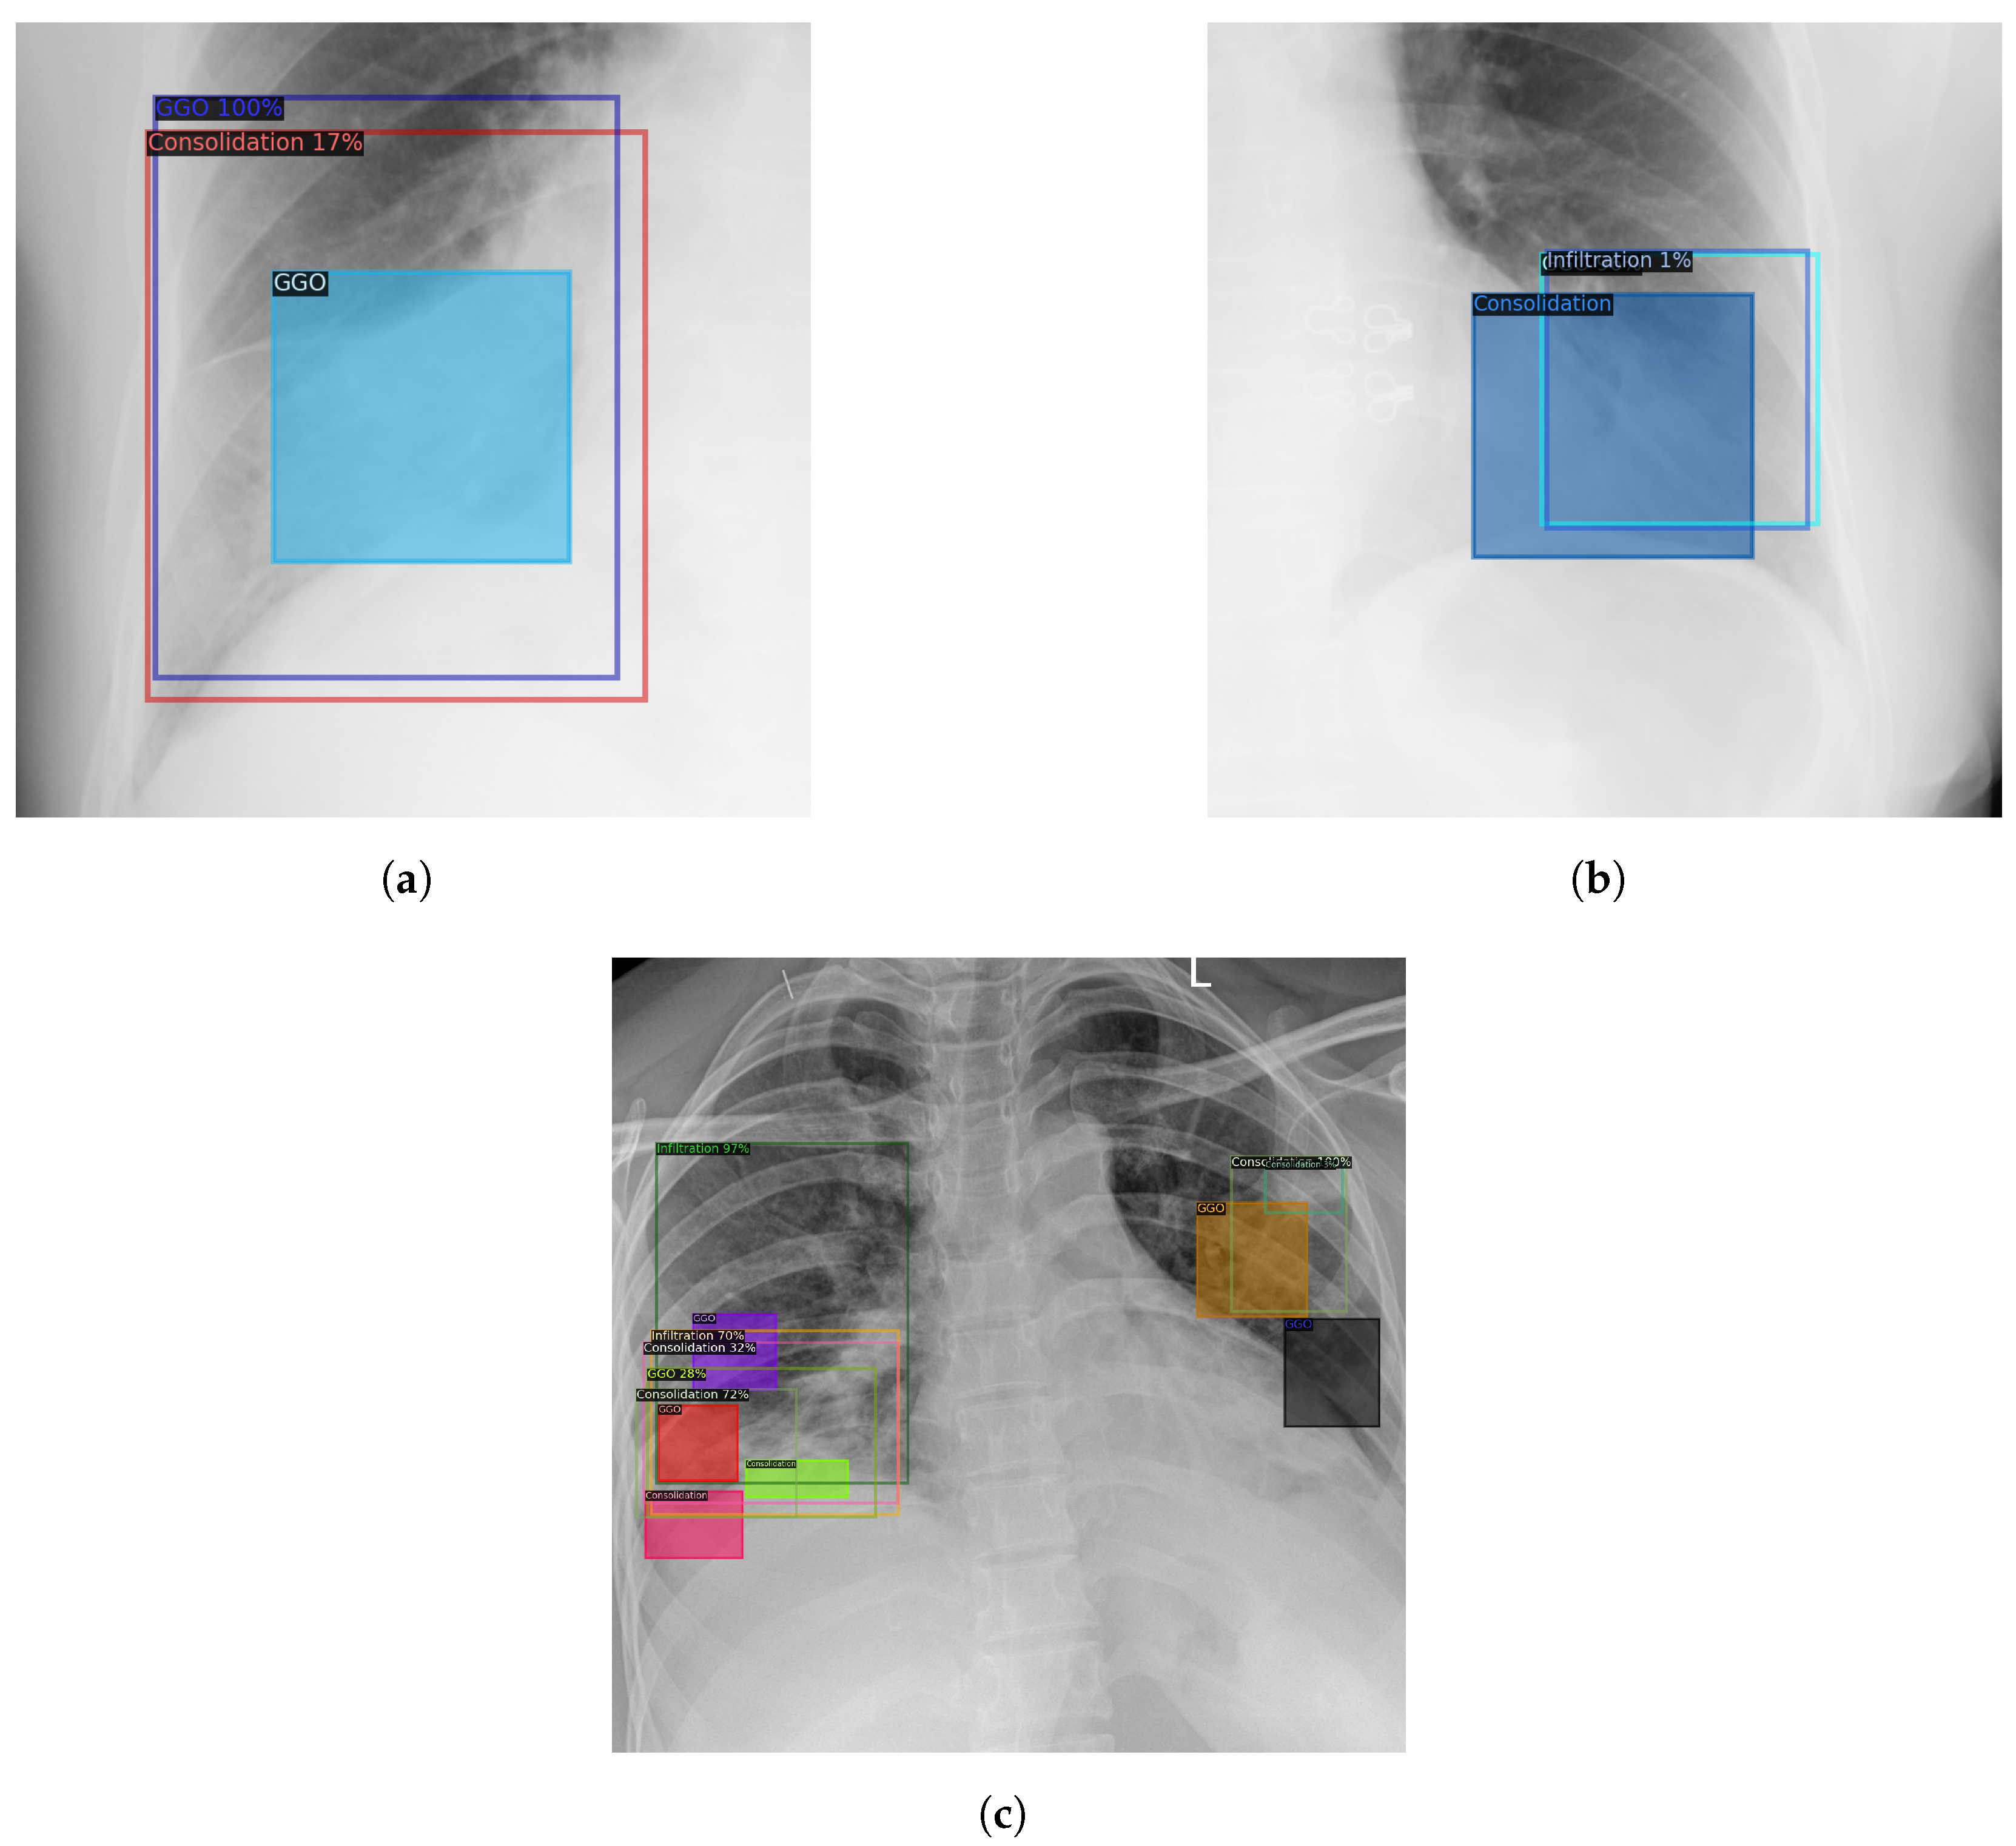

- Preliminary experiments were conducted to verify our assumption. The results confirm our findings that COVID-19 and community-acquired pneumonia damaged and caused the same injuries in the human lung; thus, we can additionally combine CXR of pneumonia to detect COVID-19-associated lung lesions (i.e., GGO (Ground-glass opacity) and Consolidation) to improve the detection accuracy.

4.2. Lung Lesion Detection